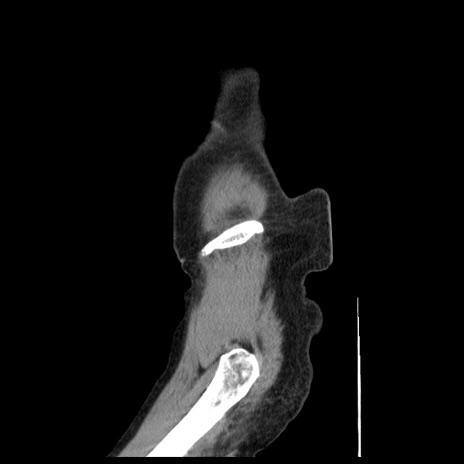

症例1(矢状断像)

【症例】80歳代女性

【主訴】腹痛

【現病歴】8時間前から腹痛あり来院。

【既往歴】糖尿病、脂質異常症、子宮体癌にて子宮全摘術

【身体所見】意識清明・会話良好だが腹痛で苦悶様、全腹部にわたって反跳痛と圧痛あり

【データ】WBC 13600、CRP 0.14、LDH 224、CK 90